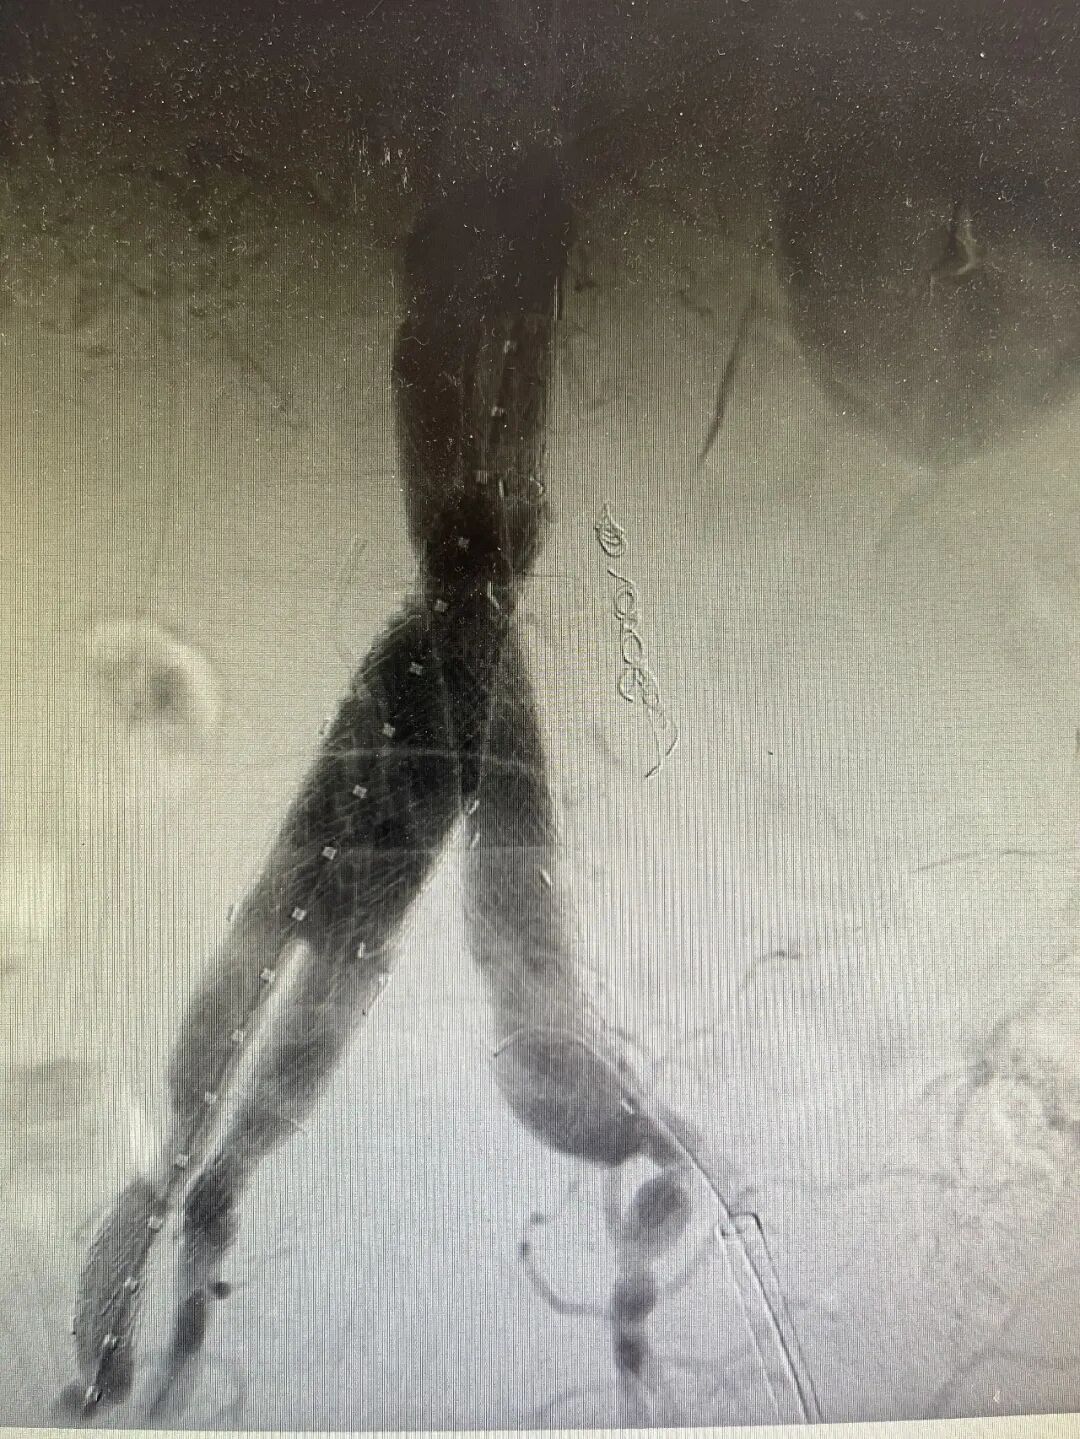

经过术前多学科会诊的详细讨论和周密规划,近日,李清乐教授与青岛医院血管外科执行主任孙念峰、主任医师孙春亮周密规划,为这两名患者实施了血管外科微创手术(IBE)。

手术最大的挑战,是如何在隔绝动脉瘤的同时,精准重建髂内动脉。采用腹主动脉分支支架、髂动脉分支支架技术重建腹主动脉、髂总动脉、髂外动脉、髂内动脉,是目前公认的既能隔绝动脉瘤、又能最大限度保留盆腔功能的最优解之一。这项技术操作复杂,对医生的技术和团队的配合要求极高,经过手术团队精细操作,手术顺利结束,患者已顺利出院。